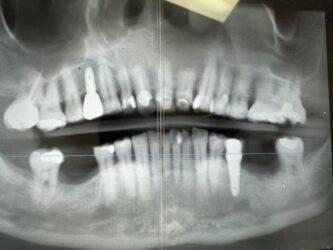

Dr. started the discussion #20 implant in the forum Complications a year ago

Hi, this implant was placed in June 2024. I have 3PAs (one from day of placement, one month later, and 9 month later). The intraoral picture of the soft tissue is from yesterday and tissue looks great… patient has no discomfort/pain either. She did have some discomfort between 2-3rd week after placement but subsided after taking…